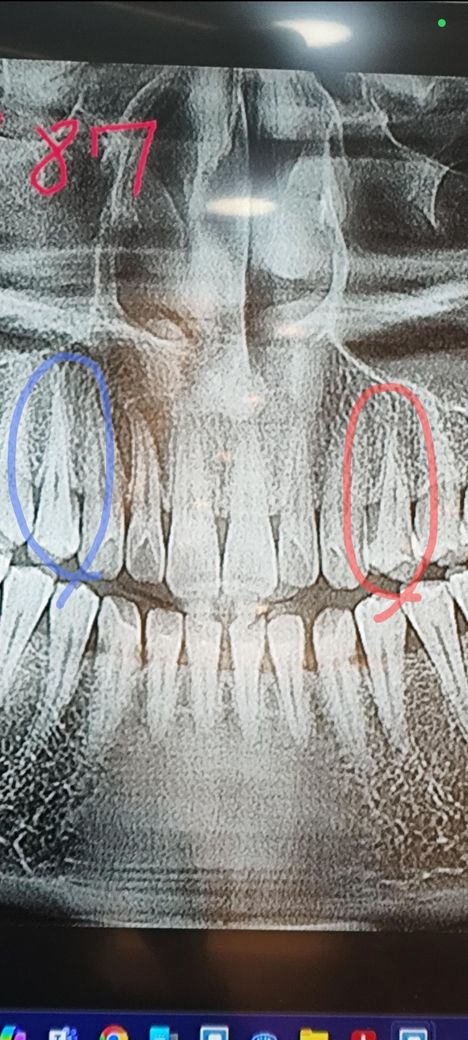

치아에 균열이 간거 같아요 뿌리에 균열이 간게 맞는지 확인한번 부탁드려요

사진상 오른쪽 빨간동그라미 치아가 아파서

오른쪽 빨깐동그라미 치아 뿌리부분이 사선으로 균열이 있진 않나요?

왼쪽 파란색 동그라미 같은위치의 3번째 작은어금니만 봐도 뿌리가 꾀크고 긴대

문제의 오른쪽 작은어금니는 뿌리부분 길이가

유난히 짧아 보이는게

사선으로 균열이 생겨서 염증등 세균이 침투해서 게속 문제를

일으키는거 아닌가 싶어요

방사선 사진만으로는 치아의 급 여부를 확인하기 어려워 보입니다. 치아의 금을 확인하기 위해서는 육안이나 그 외에 다른 도구를 이용해서 금의 여부를 판단할 수 있습니다. 치아에 금이 갔을 경우에는 음식을 먹을 때 특정 힘에 의해 치아에 강렬한 통증이 느껴지는 경우가 많습니다.

파노라마 엑스레이 사진은 왜곡, 중첩등이 많습니다. 만약 저렇게 뚜렷하게 보이는 크랙 라인이라면 신경치료 했어도 씹을때 심하게 아플겁니다.